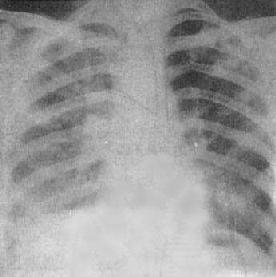

肺肿块

图3-1-12 肺肿块

右肺外围型肺癌,肿块呈分叶状,边缘清楚,密度均匀